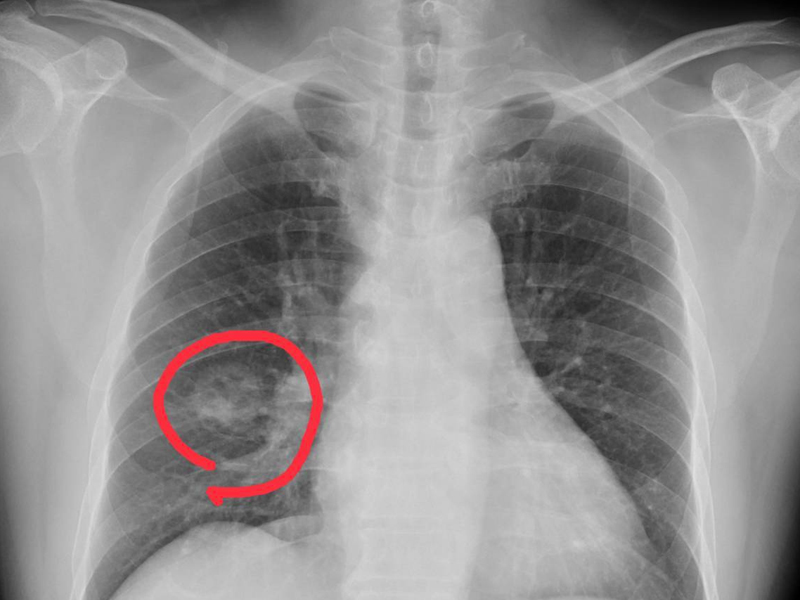

肺癌來臨並非無聲無息,提醒:手腳出現 4 種異常,可能是肺癌到來,不要大意!

1. 手指變粗

一般情況下手指變粗很可能是肺癌的信號,尤其是長期吸煙的男性朋友,要特別警惕杵狀指,也就是手指末端變粗,增生,膨大,同時還會伴有咳血、刺激性乾咳、胸痛等症狀。

2. 腿部栓塞

引起腿部栓塞的原因有很多,血栓是比較常見的一種,癌症也是其中一種。當下肢出現不明原因的栓塞,要警惕是宮頸癌、肺癌、乳腺癌的可能。

3. 雙手雙手腳麻痺

當肺部有惡性腫瘤時,由於癌細胞對肺組織的侵襲,會影響肺部的呼吸功能,導致體內氣體交換異常,導致患者全身缺氧,而人體的手腳屬於末端,這種現象尤其明顯,因此會出現手腳麻痺的症狀。

4. 關節疼痛

在肺癌晚期,腫瘤細胞可通過血液循環等途徑轉移到骨中,引起骨損傷和骨膜神經損傷,可引起局部劇烈疼痛症狀,如手足關節疼痛,也可導致病理性骨折,加重疼痛症狀。